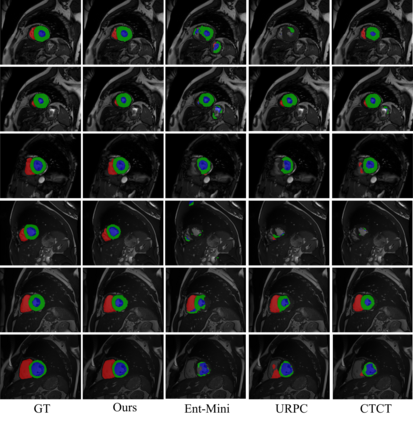

Semi-supervised medical image segmentation has attracted much attention in recent years because of the high cost of medical image annotations. In this paper, we propose a novel Inherent Consistent Learning (ICL) method, which aims to learn robust semantic category representations through the semantic consistency guidance of labeled and unlabeled data to help segmentation. In practice, we introduce two external modules namely Supervised Semantic Proxy Adaptor (SSPA) and Unsupervised Semantic Consistent Learner (USCL) that based on the attention mechanism to align the semantic category representations of labeled and unlabeled data, as well as update the global semantic representations over the entire training set. The proposed ICL is a plug-and-play scheme for various network architectures and the two modules are not involved in the testing stage. Experimental results on three public benchmarks show that the proposed method can outperform the state-of-the-art especially when the number of annotated data is extremely limited. Code is available at: https://github.com/zhuye98/ICL.git.